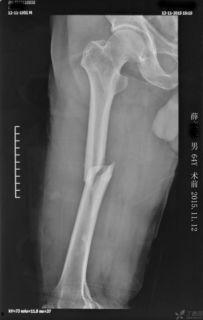

在手术前,医生会对患者进行详细的检查,确保手术的顺利进行。他们会为患者进行X光检查,了解股骨骨折的具体情况。此外,医生还会对患者进行血液检查,以确保患者没有手术禁忌症。

为了让大家更直观地了解股骨髓内钉手术,我们来看一个真实的案例。患者小李,因意外事故导致股骨骨折,经过医生诊断,决定进行股骨髓内钉手术。

手术当天,小李被送入手术室。麻醉生效后,医生开始进行手术。手术过程中,小李的家属在手术室外紧张地等待着。经过一个多小时的手术,小李的股骨髓内钉手术顺利完成。